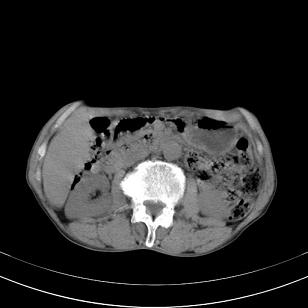

标题: 男,65岁,反复右上腹痛, [打印本页]

标题: 男,65岁,反复右上腹痛,

胃镜提示十二指肠占位